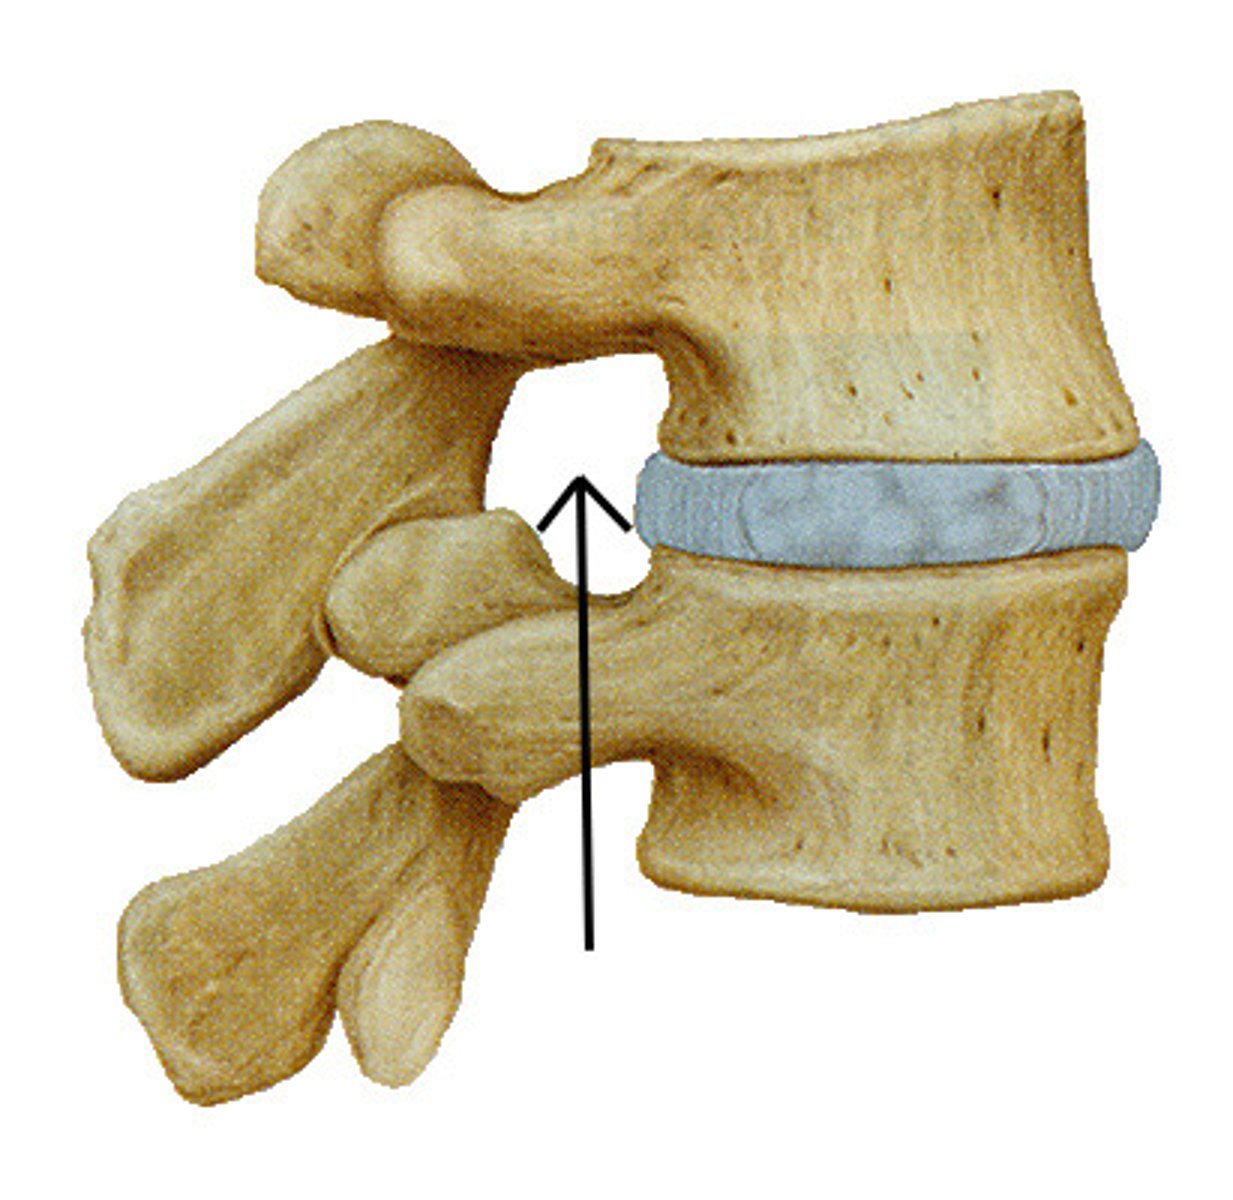

When vertebrae are stacked, the superior and inferior vertebral notches line up to form a single opening called the ______________ ________

intervertebral foramen

The intervertebral foramen allows for passage of what?

important spinal nerves, blood vessels

The THORACIC intervertebral foramina are ONLY demonstrated on what view?

true lateral

The LUMBAR intervertebral foramina are ONLY demonstrated on what view?

true lateral